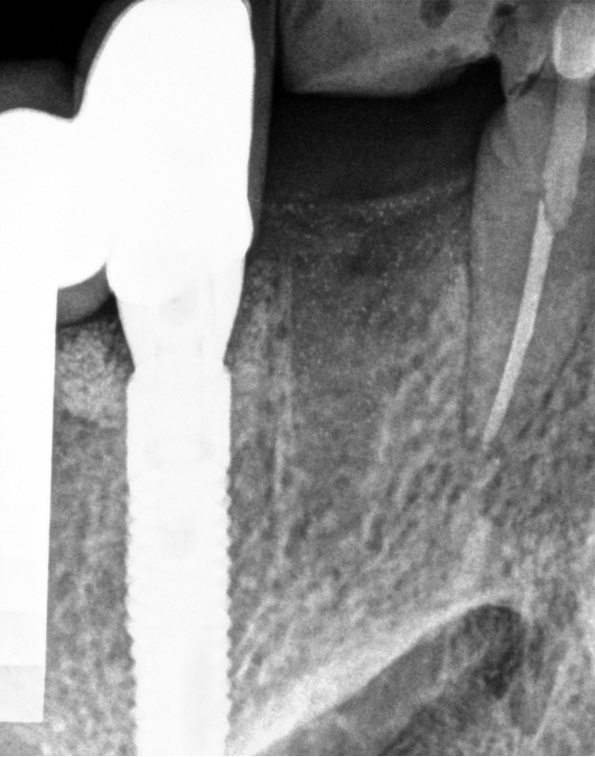

Bogata w płytki i leukocyty fibryna jest stosowana w regeneracji tkanek od ponad 15 lat. Pozytywny wpływ PRF (platelet-rich fibrin) na regenerację tkanek miękkich jest niewątpliwy, bezsporny i częściowo udowodniony w badaniach klinicznych i analizach biochemicznych. Wpływ PRF na regenerację tkanki kostnej jest obserwowany klinicznie, ale nadal niedostatecznie poznany jest mechanizm tego zjawiska.

Platelet- and leukocyte-rich-fibrin has been used in regeneration of tissue for more than 15 years. The positive influence of PRF on the regeneration of soft tissue is undoubtedly, without question and partially proven in clinical studies and biochemical analysis. Influence of PRF on regeneration of bone tissue is observed clinically but the mechanism of this phenomenon is still not sufficiently known.